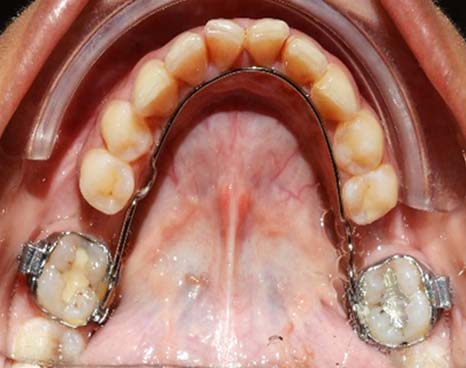

Four months later after bonding the upper arch, the lower arch was bonded along with the 3D lingual arch and further allignment of the lower arch was observed [Table/Fig-9].

Complete correction of molar uprighting and mild allignment of lower anteriors due to expansion by the 3D lingual arch.